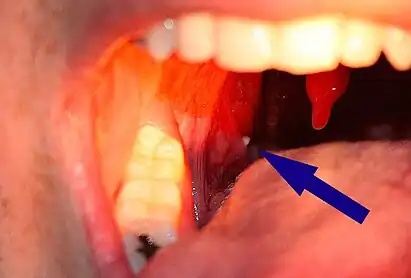

A tonsillolith lodged in the tonsillar crypt | |

Tonsil stones, also known as tonsilloliths, are mineralizations of debris within the crevices of the tonsils.[1][3] When not mineralized, the presence of debris is known as chronic caseous tonsillitis (CCT).[1] Symptoms may include bad breath,[1] foreign body sensation, sore throat, pain or discomfort with swallowing, and cough.[4] Generally there is no pain, though there may be the feeling of something present.[1] The presence of tonsil stones may be otherwise undetectable, however some people have reported seeing white material in the rear of their throat.